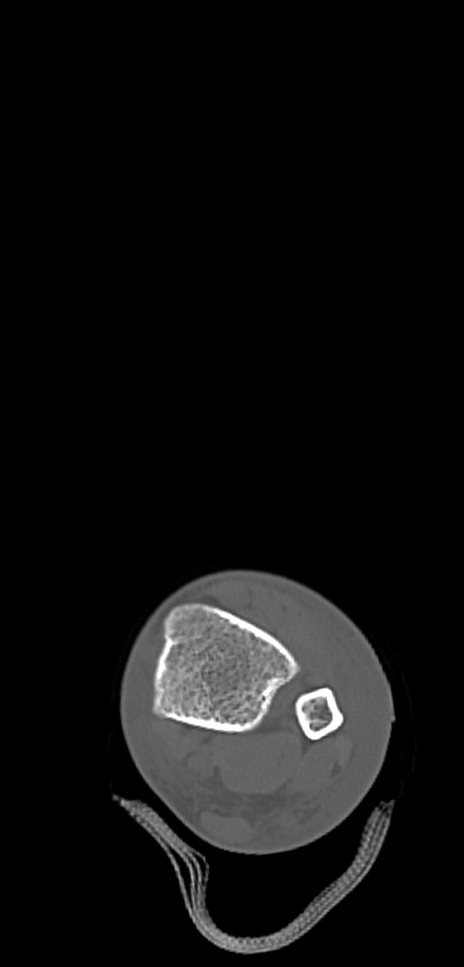

症例37 左足関節CT(横断像)

左足関節CT